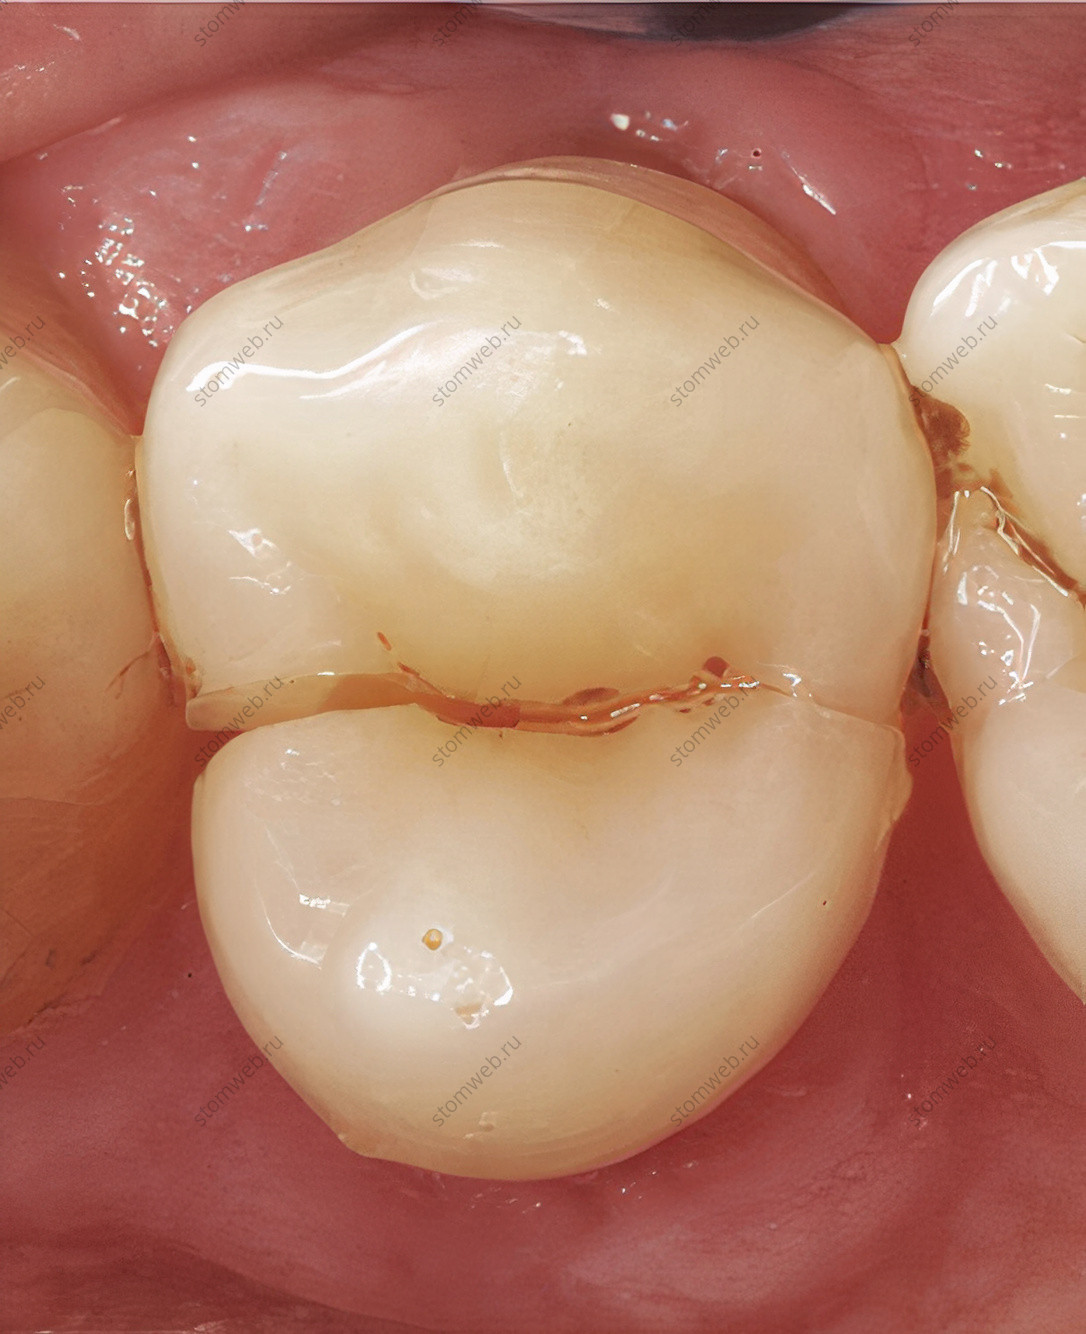

Два других термина представляют собой крайние значения переломов коронок. Линии трещин - это видимые трещины, затрагивающие только эмаль (рис. 5). Они могут распространяться на нижележащий дентин, но это обычно трудно определить. Они не связаны с симптомами, и лечение ведется по эстетическим показаниям. Другая крайность - это полный перелом зуба, который проходит через оба краевых гребня, обычно в мезио-дистальном направлении, полностью разделяя зуб на два отдельных сегмента (рис. 6). Для удобства в этой главе термин «перелом» обычно используется для различных переломов коронок.

Рисунок 6. Премоляр верхней челюсти с мезиодистальным расколом